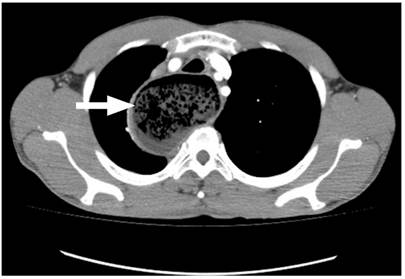

A 42-year-old male driver, with no relevant medical history, consulted due to 3 years of progressive dysphagia initially for solids and then for liquids, and regurgitation, with a worsening of symptoms in the last 4 months associated with a weight loss of 15 kg (Eckardt score 9). On admission, the patient showed signs of severe malnutrition and halitosis, without dyspnea, peripheral lymphadenopathy, visceromegaly, or ascites. A nasogastric intubation was carried out, obtaining abundant food drainage. A chest x-ray was performed in which an apparent mediastinal mass displacing the midline was observed (Figure 1). In view of this finding and persistent dry cough, an enhanced chest computed tomography (CT) scan was performed, in which megaesophagus and suggestive findings of achalasia were reported, but no neoplastic involvement of the gastroesophageal junction could be ruled out (Figure 2).

Figure 2 Enhanced chest CT scan. Esophageal dilation, with a maximum transverse diameter of 7 cm, with tortious margins. Heterogeneous material suggestive of food content (thick arrow). Source: Gastroenterology Unit. Hospital Universitario San Ignacio. Bogotá D.C. Colombia.